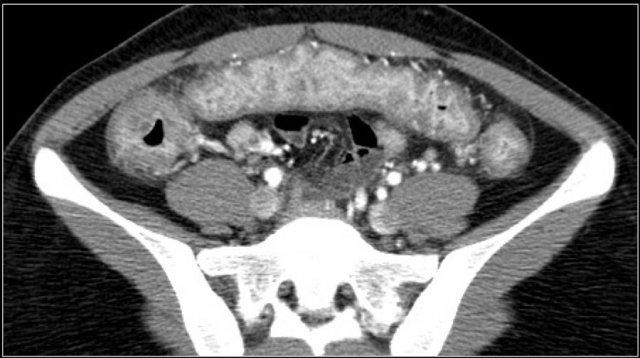

Đây là hình ảnh của một bệnh nhân mắc PMC.

Có hình ảnh cổ trướng và thành ruột ngấm thuốc mạnh kèm phù nề lớp dưới niêm mạc và phù nề mạc treo đại tràng.

Đoạn ruột giãn ở hố chậu phải thực chất là đại tràng sigma dư thừa.

Các dấu hiệu trên CT bao gồm:

- Dày thành ruột toàn chu vi và lan tỏa kèm phù nề lớp dưới niêm mạc.

- Các nếp bờm đại tràng nổi bật.

- Dày thành ruột dạng polyp lệch tâm.

- Bờ lòng ruột không đều, xù xì.

- Thuốc cản quang đường uống có thể bị giữ lại giữa các nếp dày, tạo hình ảnh giả đường rò.